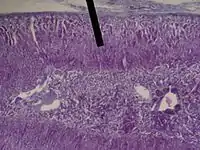

The zona fasciculata (sometimes, fascicular or fasciculate zone) constitutes the middle and also the widest zone of the adrenal cortex, sitting directly beneath the zona glomerulosa. Constituent cells are organized into bundles or "fascicles".